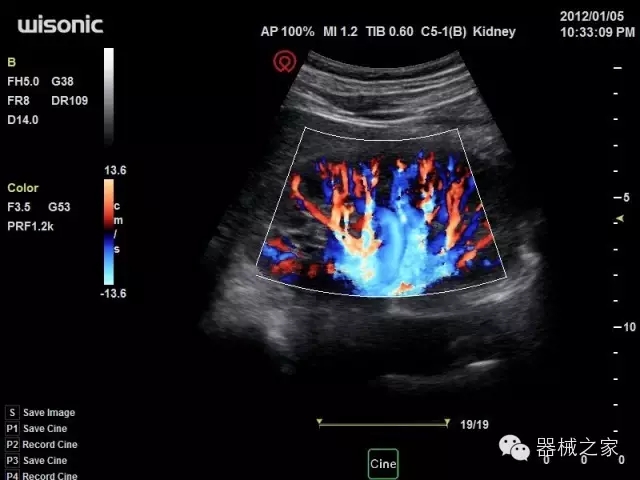

經(jīng)典產(chǎn)品:四葉草

臨床圖片賞析

產(chǎn)品特點(diǎn)

·全球目前唯一一款配備主機(jī)雙探頭接口,整機(jī)重量(含電池)在5公斤以內(nèi)的便攜式彩超;

·一款互聯(lián)網(wǎng)彩超,只要有手機(jī)信號(hào)的地方就可以非常方便地實(shí)現(xiàn)遠(yuǎn)程會(huì)診和病案調(diào)?。?/span>

·鎂鋁合金外殼,堅(jiān)固可靠耐用;

·獨(dú)有的HoloTM PW 實(shí)時(shí)3取樣門PW成像技術(shù),精確進(jìn)行血管診斷;

·一鍵優(yōu)化B、Color、PW,Auto Doppler自動(dòng)識(shí)別血管位置、偏轉(zhuǎn)角度等,提高工作效率;

·30°超廣角精細(xì)偏轉(zhuǎn)成像技術(shù),更優(yōu)異的頻譜圖像;

·W+智能搜索引擎,快速尋找圖像;

·SSD、USB3.0保障開機(jī)快,導(dǎo)出圖像更快,減少等待時(shí)間;

·WIFI、網(wǎng)口、3G,多重聯(lián)網(wǎng)方式,全天候保障云端備份,不再擔(dān)心圖像丟失;

CFDA注冊證編號(hào)

·粵械注準(zhǔn)201522231208